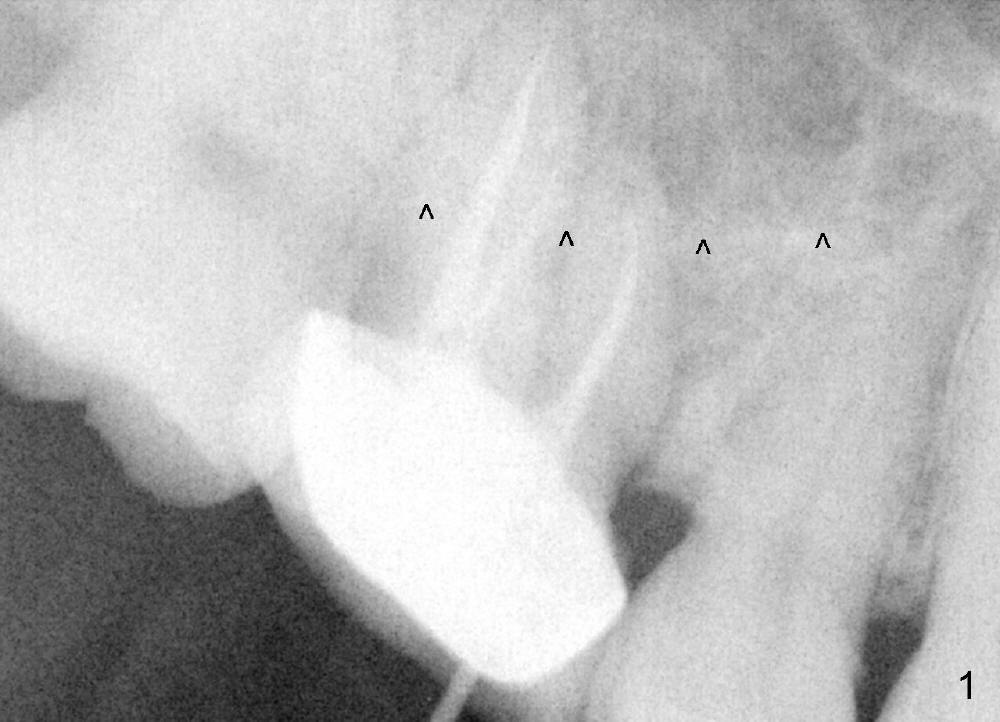

The tooth #3 of a 45-year-old man has endo failure (Fig.1), which shows that the sinus floor (^) is lower than the root tips. Fig.2 is taken a few days post extraction. Note low bone density in the socket, which is the basis for bone condensation. Five months later the patient returns for implantation. A ~12 mm incision is place in the edentulous ridge. The osteotomy forms by using osteotomes (rounded tapered 2-4 mm), followed by insertion of a 4.5x14 mm tap at the depth of 11 mm (Fig.3). It appears that the tip of the tap is in the sinus, but the top of the osteotomy has solid bone when the tap is removed. The bone is being expanded until 7x14 mm tap at the depth of 11 mm (Fig.4). The roof of the osteotomy is still intact. It appears that bone expansion intentionally lifts the sinus floor.